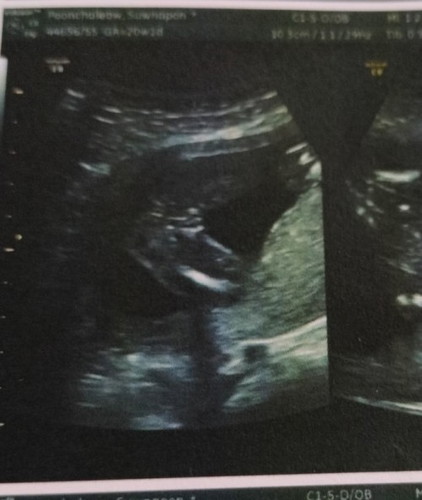

แบบนี้น้องเพศหญิงมั้ยค่ะ

หมอแจ้งว่าหญิง แต่ก็แอบหวั่นว่าจะได้ชาย ไม่กล้าซื้อของเตรียมเลยค่ะ 😂😂😂#ขอบคุณล่วงหน้านะคะ

ผู้หญิงค่ะแม่ ถ้าผู้ชายจะเห็นจู๋แบบนี้เลยค่ะ

เราว่าหญิงคะ นี้ของเราตอน20วีค